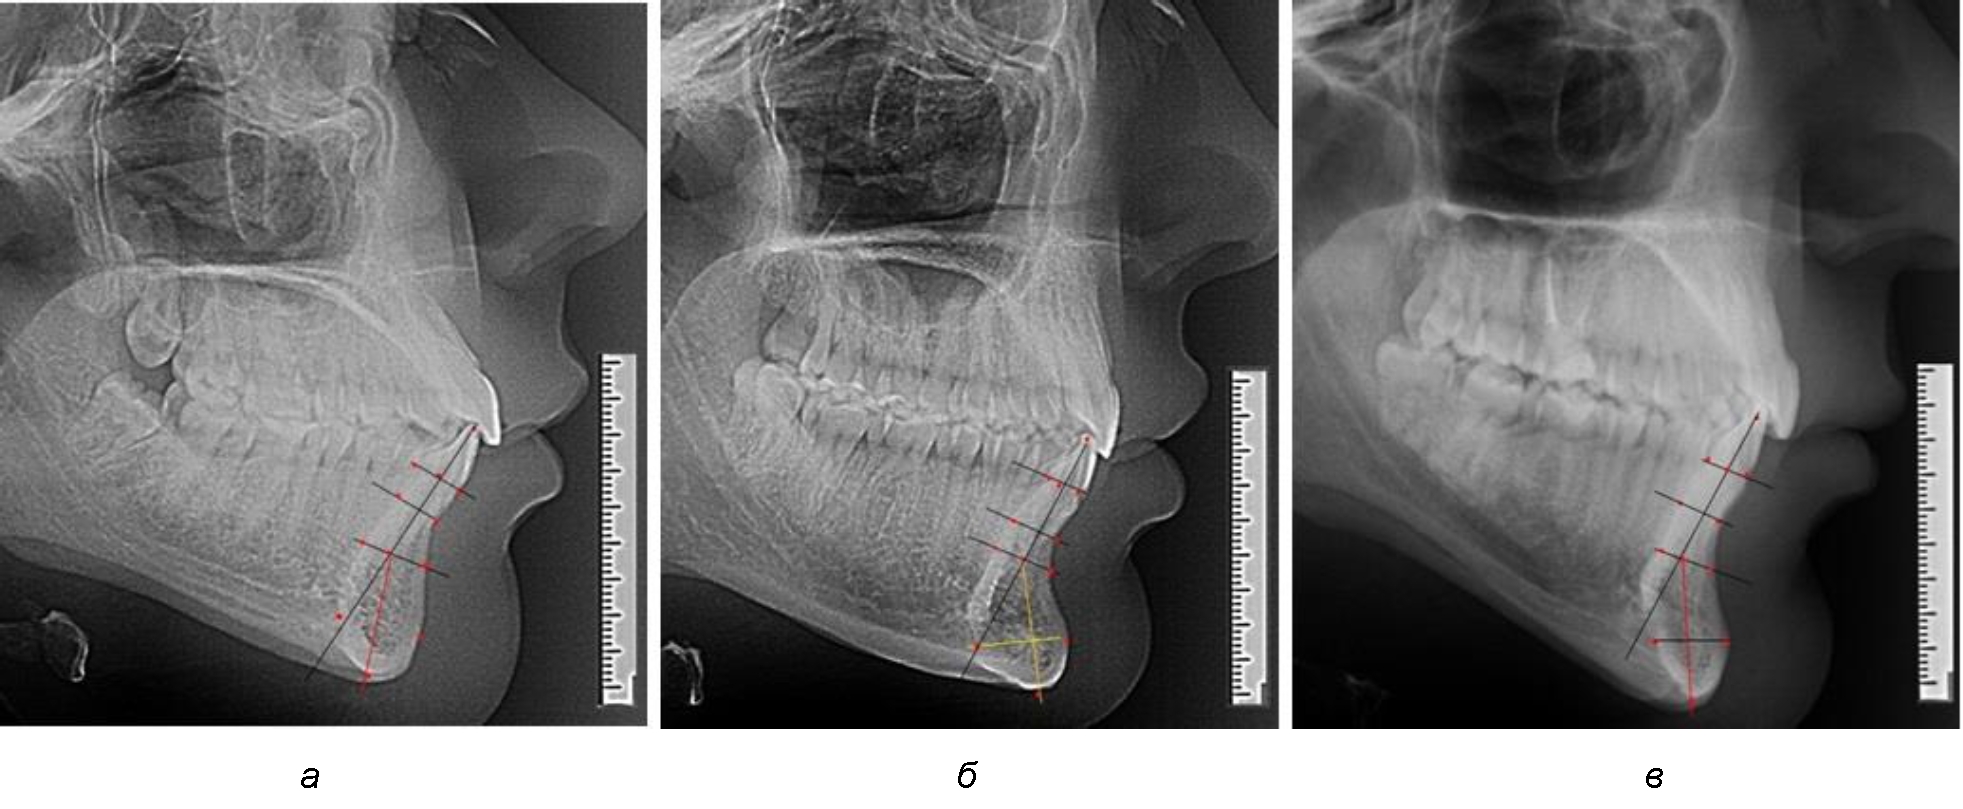

При анализе боковых телерентгенограмм использовали фрагменты гнатической части, на которых оценивали вертикальные и сагиттальные параметры резцового нижнечелюстного сегмента, на который наносили те же ориентиры, что и при анализе нативных препаратов и их рентгенограмм.

При необходимости и/или возможности проведения КЛКТ-исследования проводили анализ с сопоставлением фрагмента, что повышало точность диагностических мероприятий (рис. 2).

Рис. 2. Фрагменты ТРГ с ориентирами для измерения параметров резцового сегмента (а) и с наложением фрагмента КЛКТ (б)

При анализе полученных данных обращает на себя внимание факт того, что из вертикальных параметров зубоальвеолярной части сегмента наиболее вариабельным является размер между апикальными точками Downs и Schwarz (BSM–B), который составлял (6,79 ± 0,54) мм, при величине сигмального отклонения – 2,35. Также большая ошибка репрезентативности и сигмальное отклонение было отмечено при оценки ширины подбородочного выступа. В связи с этим встречались варианты резцовых сегментов нижней челюсти различные как по ширине, так и по высоте, а также по расхождению положения апикальных точек по Downs и Schwarz (рис. 3).

Рис. 3. Варианты среднего (а), широкого (б) и узкого (в) нижнечелюстного резцового сегмента

Варианты резцовых сегментов нижней челюсти различные как по ширине, так и по высоте, а также по расхождению положения апикальных точек по Downs и Schwarz представлены на рис. 4.

Рис. 4. Особенности нижнечелюстного резцового сегмента на ТРГ у людей при среднем (а), широком (б) и узком (в) вариантах